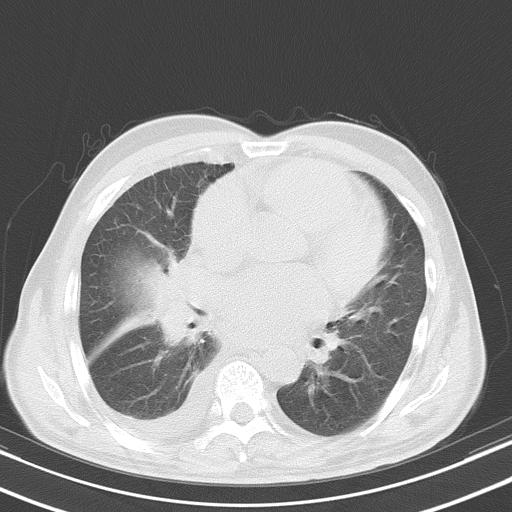

以下是引用zjzjr在2010-3-21 17:39:00的发言:[br]右下中心型肺癌并阻塞性肺炎/不张,纵膈淋巴结肿大,右侧大量胸腔积液,左侧少量胸腔积液

以下是引用zxl51642在2010-3-21 17:06:00的发言:[br]右下中心型肺癌并阻塞性肺炎/不张,纵膈淋巴结肿大,右侧大量胸腔积液,左侧少量胸腔积液,少量腹水。建议纤维支气管镜进一步检查。